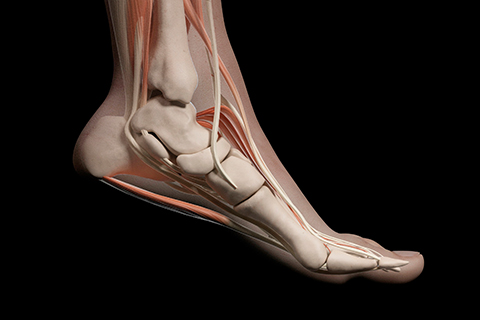

• 손목충돌증후군

손목의 척측(새끼손가락이 있는 손목 끝)에 과도한 하중이 반복적으로 가해질 때 생기는 삼각섬유연골 파열입니다.

손목충돌증후군 치료방법

• 비수술적 치료 약물치료, 주사치료, 물리치료, 체외충격파 치료

• 수술적 치료 원위척골 단축술